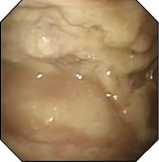

近年来,贵州航天医院各科室紧跟医学前沿,不断强技术、补短板,大力开展新技术、新项目,完成了许多高精尖、高难度、本地区“首例”的技术,填补了医院医疗技术空白,满足了群众日益增长的医疗需求。 贵州航天医院呼吸与危重症医学科是贵州省内呼吸疾病治疗规模最大,诊疗项目最全的呼吸疾病品牌科室,呼吸介入技术达到了全国先进水平,在贵州省内处于领先的地位。 本期,我们将为大家带来呼吸与危重症医学科特色技术——内科胸腔镜技术诊断和治疗胸腔疾病。 案例分享 患者苟某某,因劳累、气促,不明原因胸腔积液在某县一医院采取反复抽水等治疗手段效果不佳,当地医院考虑到患者年龄大(77岁),基础疾病较多,病情复杂,结合当地诊疗水平能力情况,建议转到上一级医院诊治,通过我院与该院建立的呼吸专科联盟绿色通道转入了我院。 患者入院后,呼吸与危重症医学科第一时间复查胸部CT,提示:右肺中叶、左肺感染,纤维化灶,左侧中量胸腔积液,右后侧胸膜轻度增厚,心包少量积液;并完善心电图、血常规、凝血功能、生化指标等术前检查。经科室专家团队集体讨论,得出患者左侧胸腔积液可能原因:结核?恶性?其他?冠心病、心功能不全、高血压病3级(高危组)、陈旧性肺结核复发?肺部感染;为进一步明确诊断,在充分评估、做好术前准备及应急预案、与患者及家属沟通的情况下,决定为患者进行内科胸腔镜检查术。 科室在患者入院第3天便实施了内科胸腔镜检查术,经检查取活检,病理不排除胸膜间皮瘤,送遵义医科大学附属医院病理会诊后诊断:胸膜间皮瘤。明确诊断后,科室专家团队为患者制定了个体化的治疗方案,患者病情很快得到有效控制,最终满意出院。半年后,医院通过电话回访,患者病情稳定,生活质量明显改善。 什么是内科胸腔镜 内科胸腔镜(medical thoracoscopy,MT)是一项微创诊断和治疗胸腔疾病的重要技术。主要应用于无创方法不能确诊的胸腔积液和胸膜疾病,通过局部麻醉后在胸壁做一个小切口,插入胸腔镜,直接观察胸膜、肺表面、纵隔等部位的病变情况,可进行活检、粘连松解及胸膜固定等操作。具有创伤小、恢复快、诊断准确性高等优点。 内科胸腔镜原理 内科胸腔镜是一项利用现代光学技术和成像技术的侵入性操作技术,应用电子支气管镜、硬质或软硬结合(半硬)的胸腔镜的一种电子内窥镜,末端装有连接着显示屏的微型摄像头。通过胸壁1-2cm左右的小切口,将内科胸腔镜及专用器械(戳卡套管)通过小切口进入胸腔,微型摄像头将胸腔内的情况投射到显示屏幕上,医生可以通过镜头全面、直观地观察患者胸腔内情况,了解胸膜病变确切位置和形态改变,还可对胸膜上的病变进行活检及治疗的操作技术,安全、微创、几乎无痛地“揭秘”不明原因的胸腔积液。 内科胸腔镜技术优势 (一)安全性高:仅需局部浸润麻醉,并发症发生率相对较低,对患者的身体条件要求较低。 (二)操作简便:操作时间短,痛苦少,患者耐受好。 (三)微创性:切口小,对患者身体损伤小,术后疼痛轻,恢复快。 (四)高分辨率成像:清晰显示胸腔内细微病变,提高诊断准确性。 (五)可直视操作:直接观察病变,进行精准活检和治疗。 (六)适用范围广:可用于不明原因胸腔积液、胸膜疾病、肺部疾病等的诊断和治疗。 (七)费用低:与外科胸腔镜比较费用低廉。 内科胸腔镜技术是贵州航天医院呼吸专科和呼吸介入诊疗优势的一部分,在2016年率先开展了内科胸腔镜技术,年手术量约100余例,已建立了快速、精准、规范、有效的一体化诊疗服务体系。目前呼吸与危重症医学科内科胸腔镜技术广泛应用于不明原因胸腔积液、气胸、脓胸的诊断和肺癌、弥漫性恶性胸膜间皮瘤等的分期,恶性或复发性胸腔积液、早期脓胸、自发性顽固性气胸的治疗。 镜下常见表现:单发或多发结节、灰白色弥漫性粟粒样结节、胸膜充血、水肿、胸膜增厚及纤维分隔或粘连带形成。 诊断方面: 胸腔积液的病因诊断。内科胸腔镜对恶性胸腔积液的诊断率可高达90%以上,胸腔镜对结核性病变诊断率极高,几乎达到96%以上。 腺 癌 恶性淋巴瘤 软骨肉瘤胸膜转移 滑膜肉瘤胸膜转移 结核性胸膜炎 治疗方面: 脓胸 肺大泡 贵州航天医院 呼吸与危重症医学科学科带头人 廖江荣 国务院政府特殊津贴专家 二级教授 主任医师 贵州航天医院副院长 国家级学术任职: 第二届中国医药教育协会介入微创专业委员会呼吸分会副主任委员 中国抗癌协会肿瘤微创治疗专业委员会常务委员 中国防痨协会结核病转化医学专业分会常务委员 第一届中国人体健康科技促进会呼吸介入专委会常务委员 中国医疗保健国际交流促进会结核病学分会第三届委员会常务委员 中国抗癌协会肿瘤微创治疗专业委员会粒子治疗学组第四届委员会委员 中华医学会结核临床专业委员会内镜介入委员 中华医学会放射学分会第十五届委员会介入学组呼吸系统介入专业委员会委员 北京健康促进会中青年专家委员会胸部疾病精准活检分委会副主任委员 中国医师协会介入医师分会第二届委员会肿瘤消融专业委员会委员 中国结核病防治综合质量控制专家指导委员会委员 亚洲冷冻治疗学会常务委员 世界内镜医师协会呼吸内镜协会常务理事 内镜临床诊疗质量评价专家委员会委员 “西部呼吸介入联盟”副理事长 专业擅长: 贵州航天医院 呼吸与危重症医学科简介 贵州航天医院呼吸与危重症医学科以呼吸危重症和介入呼吸病学为强力推手,以肺部感染性疾病及肺癌、肺小结节的早期精准诊疗、慢性呼吸疾病康复治疗为特色,以人才团队建设为核心的科室发展模式,现已成为省内呼吸疾病治疗规模最大,诊疗项目最全的呼吸疾病品牌科室。是贵州省医学重点学科、临床医学重点专科建设单位,遵义市首批呼吸重点学科、重点专科建设单位。是国家卫健委能力建设和继续教育肿瘤微创介入建设中心、贵州省县级医院微创介入培训中心、遵义市呼吸疾病临床医学中心。是国家呼吸医疗质量控制与管理哨点医院、遵义市呼吸内科专业医疗质量控制中心。是中国医药教育协会介入微创呼吸分会呼吸介入技术培训中心单位;国家卫健委海医会呼吸分会ROSE专委会“诊断性介入肺脏病学快速现场评价”培训基地;中国肺癌防治联盟“贵州航天医院肺结节诊治”分中心,中国人体健康科技促进会呼吸介入技术培训基地,贵州省中西医结合会呼吸学分会呼吸介入专委会主委单位。 基本情况 平均每年开展气管镜诊疗约4000例,经皮肺穿刺介入诊疗近千例,开展的项目包括经支气管镜(软、硬)下冷冻、氩气刀、高频电刀、球囊扩张、支架置入、超声内镜诊疗等气道介入诊疗技术,经皮肺穿刺活检及肿瘤消融术(微波、冷冻)、ROSE技术、内科胸腔镜诊疗及经血管介入诊疗技术,且多项呼吸介入诊疗技术在省内处于领先水平。 诊疗范围 航天医院呼吸专科擅长:致力于呼吸系统感染性、疑难性疾病的介入快速精准诊疗;肺癌与肺小结节早期精准诊疗水平项目提升。擅长于呼吸系统(肺)疑难病的诊断及危重病的救治,尤其在肺癌、肺小结节的早期诊断;肺癌综合靶向治疗;肺结核综合诊疗;肺部疾病的介入诊疗在省内处于前沿水平。 咨询热线 (一)呼吸与危重症医学科一病区 医生办公室:27677317 护士站:28614217 (二)呼吸与危重症医学科二病区 医生办公室:28691274 护士站:28690442 (三)呼吸与危重症医学科三病区 医生办公室:28692417 护士站:28690461 (四)呼吸与危重症医学科四病区 医生办公室:28616402、27677582 护士站:28614987、27677862